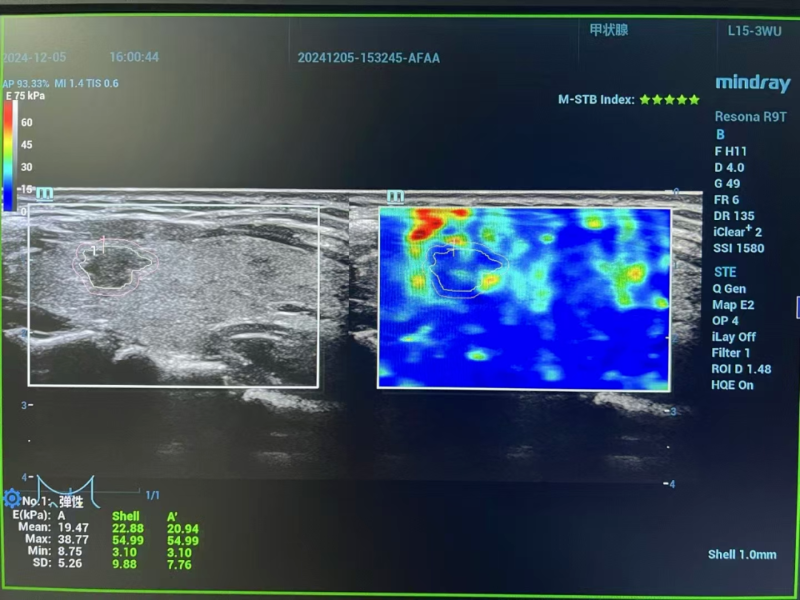

術前評估階段,專家團隊啟用高分辨率頸部超聲與先進磁共振成像技術,全方位、多維度掃描剖析。影像數據精準揭示:李女士左側甲狀腺結節小于1厘米,其包膜間距超2毫米,周邊組織未現侵襲跡象,淋巴結轉移亦無跡可尋。經嚴格篩選,甲狀腺微小乳頭狀癌微波消融手術指征確鑿無疑,為后續精準施治筑牢根基。

術后超聲造影檢查喜傳捷報:消融區域嚴密包繞癌灶,癌細胞無處遁形。李女士嗓音清晰如初,頸部痛感幾近于無,僅留微小創口,外觀幾無影響,身心恢復情況良好,術后次日即達出院標準,順利回歸生活正軌。